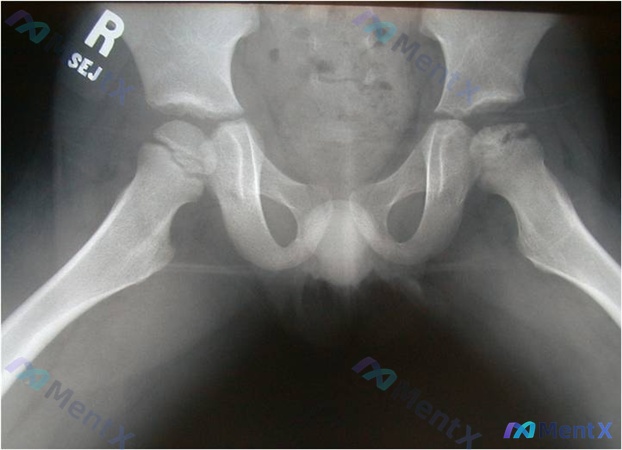

病例资料整理 患者信息:6 岁男童 主诉:左腿跛行伴疼痛 影像学表现(X 光): - 双侧髋关节正位片 - 右侧:股骨头骨骺形态正常,圆润度好 - 左侧:股骨头骨骺密度增高、扁平、碎裂,边缘不规则,呈“蘑菇状”改变;股骨颈轻度增粗;Shenton 线中断 讨论焦点 这份病例的影像学表现高度提示左侧股...